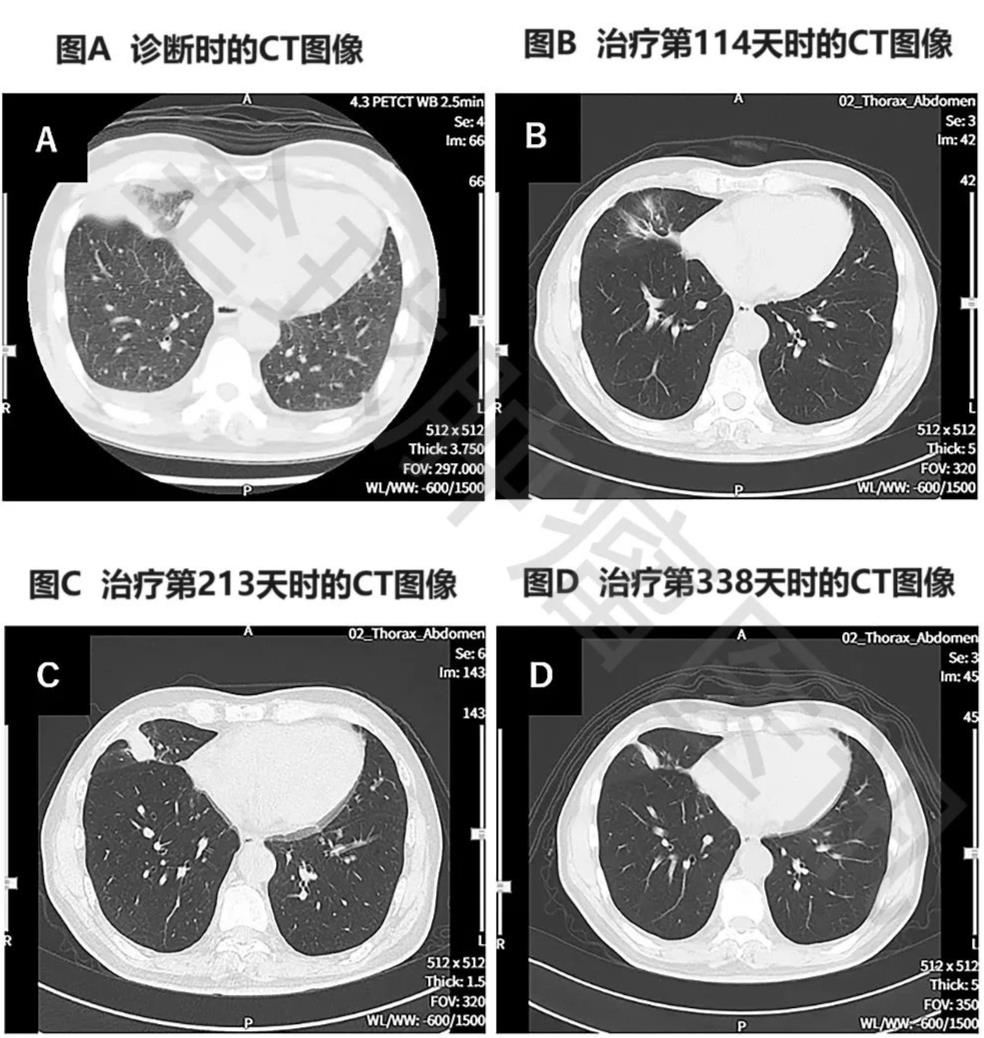

3、胸部CT显示:该患者在治疗第114天,复查胸部CT显示,肿瘤明显缩小(详见图2)。

图 治疗前后胸部CT图像对比

▲图源“Cureus”,版权归原作者所有,如无意中侵犯了知识产权,请联系我们删除

注:

①图A示:原发性右下肺癌,同时伴左右胸腔积液。

②图B示:原发病灶几乎消失。

③图C示:原发病灶存在一定程度的复发。

④图D示:原发性及复发性病灶均缩小。